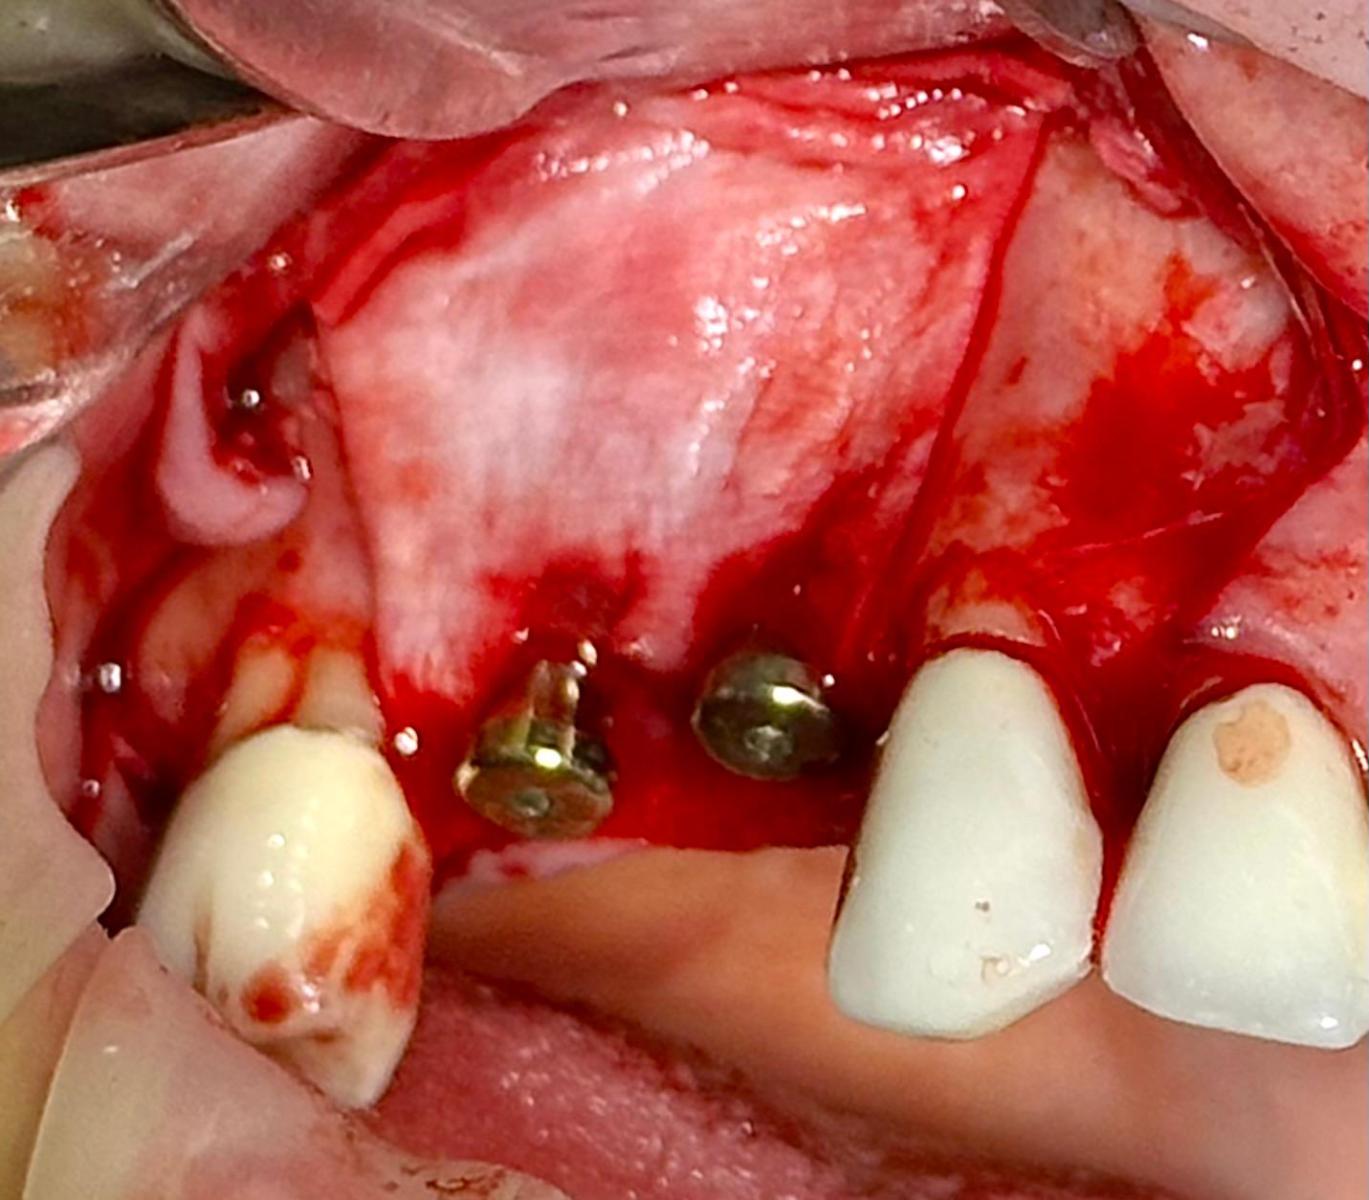

Immediate implant placement with simultaneous bone augmentation and connective tissue grafting. The case will be completed with crown lengthening, veneer replacement, and soft tissue optimisation to achieve ideal emergence profiles.